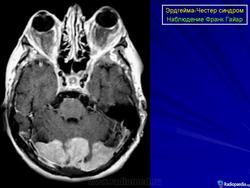

Эрдгейма - Честера болезнь.

Болезнь (или синдром) Эрдгейма-Честера является редким заболеванием. Это гистиоцитоз клеток без островков Лангерганса (небольшие скопления клеток, рассеянные по поджелудочной железе, которые секретируют гормоны инсулин и глюкагон. Существуют три гистологических типа этих клеток: альфа-, бета- и дельта-клетки; они соответственно производят глюкагон, инсулин и соматостатин), затрагивающая лиц среднего возраста, описанная впервые Уильямом Честером и Якобом Эрдгеймом в 1930 году.

Болезнь Эрдгейма-Честера характеризуется ненормальным разростанием лейкоцитов особого типа, гистиоцитов (также называются макрофаги соединительных тканей), что приводит к невозможности фильтрации соединительных тканей, в частности костного мозга трубчатых костей.

Просмотр увеличенной версии (177K)